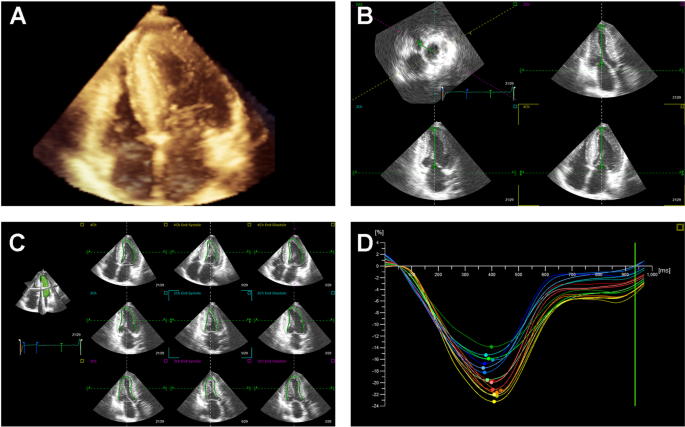

Cardiovascular Ultrasound